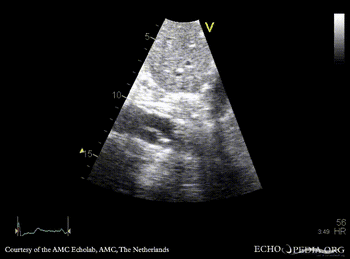

30 Aortic dissection

E00245.gif

Subcostal view: dissection flap in abdominal aorta